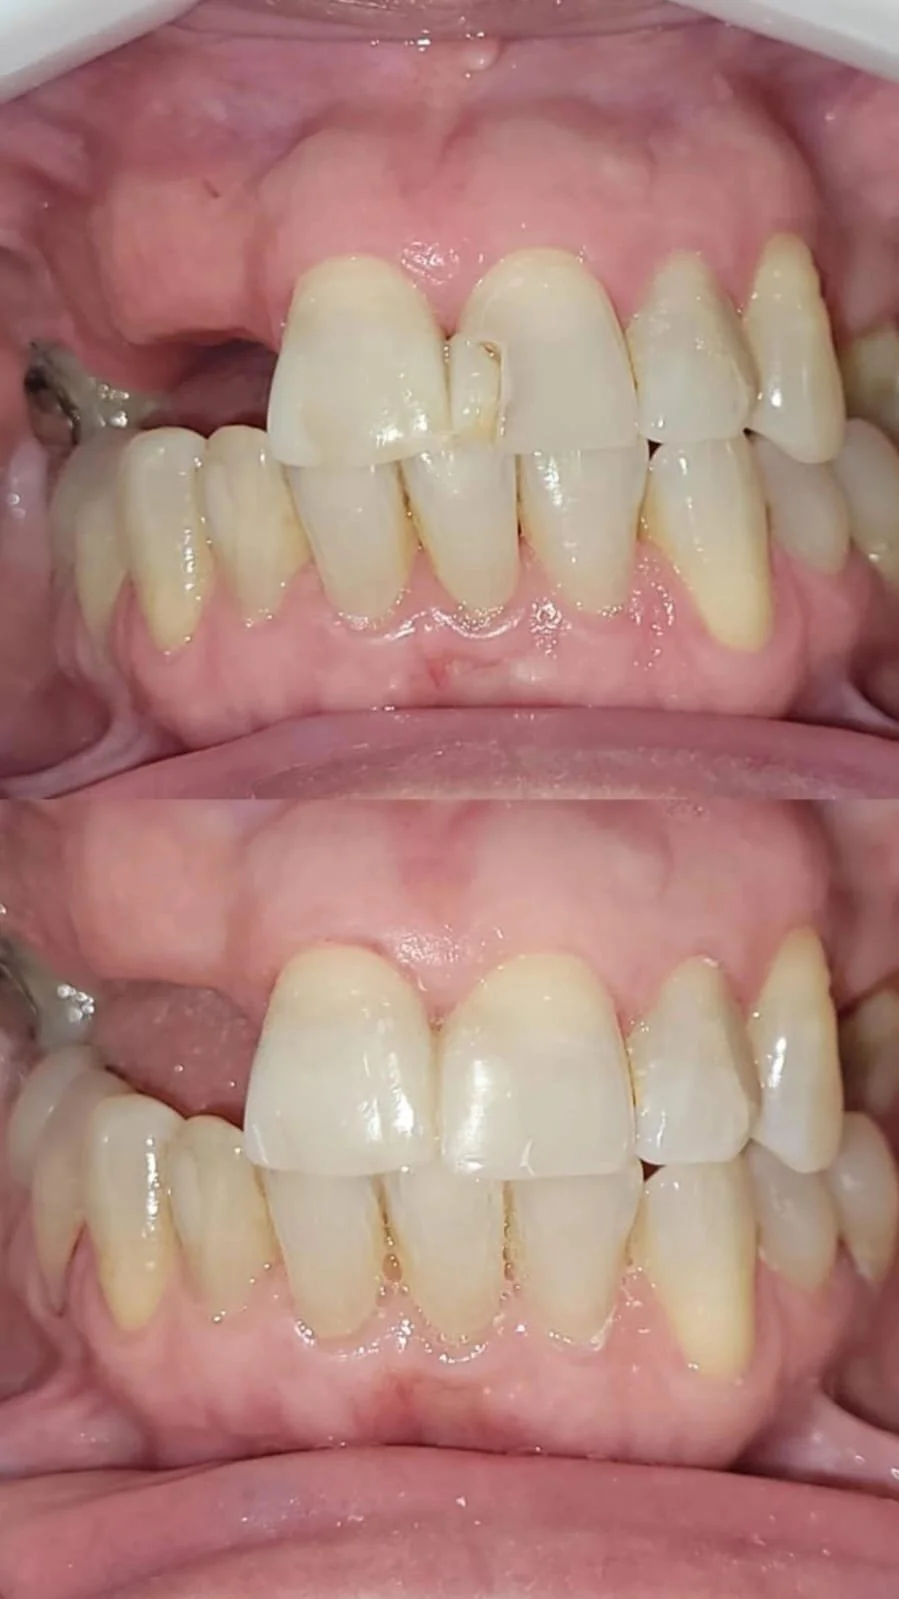

Mi practica se centra en la rehabilitación oral, con un enfoque clínico centrado en devolver funcionalidad, armonía y estética a la sonrisa. Cada caso lo abordo de forma personalizada, buscando siempre resultados predecibles, duraderos y de alto nivel. La precisión, el diseño digital y la atención al detalle son pilares fundamentales en mi trabajo.

Experiencias de pacientes